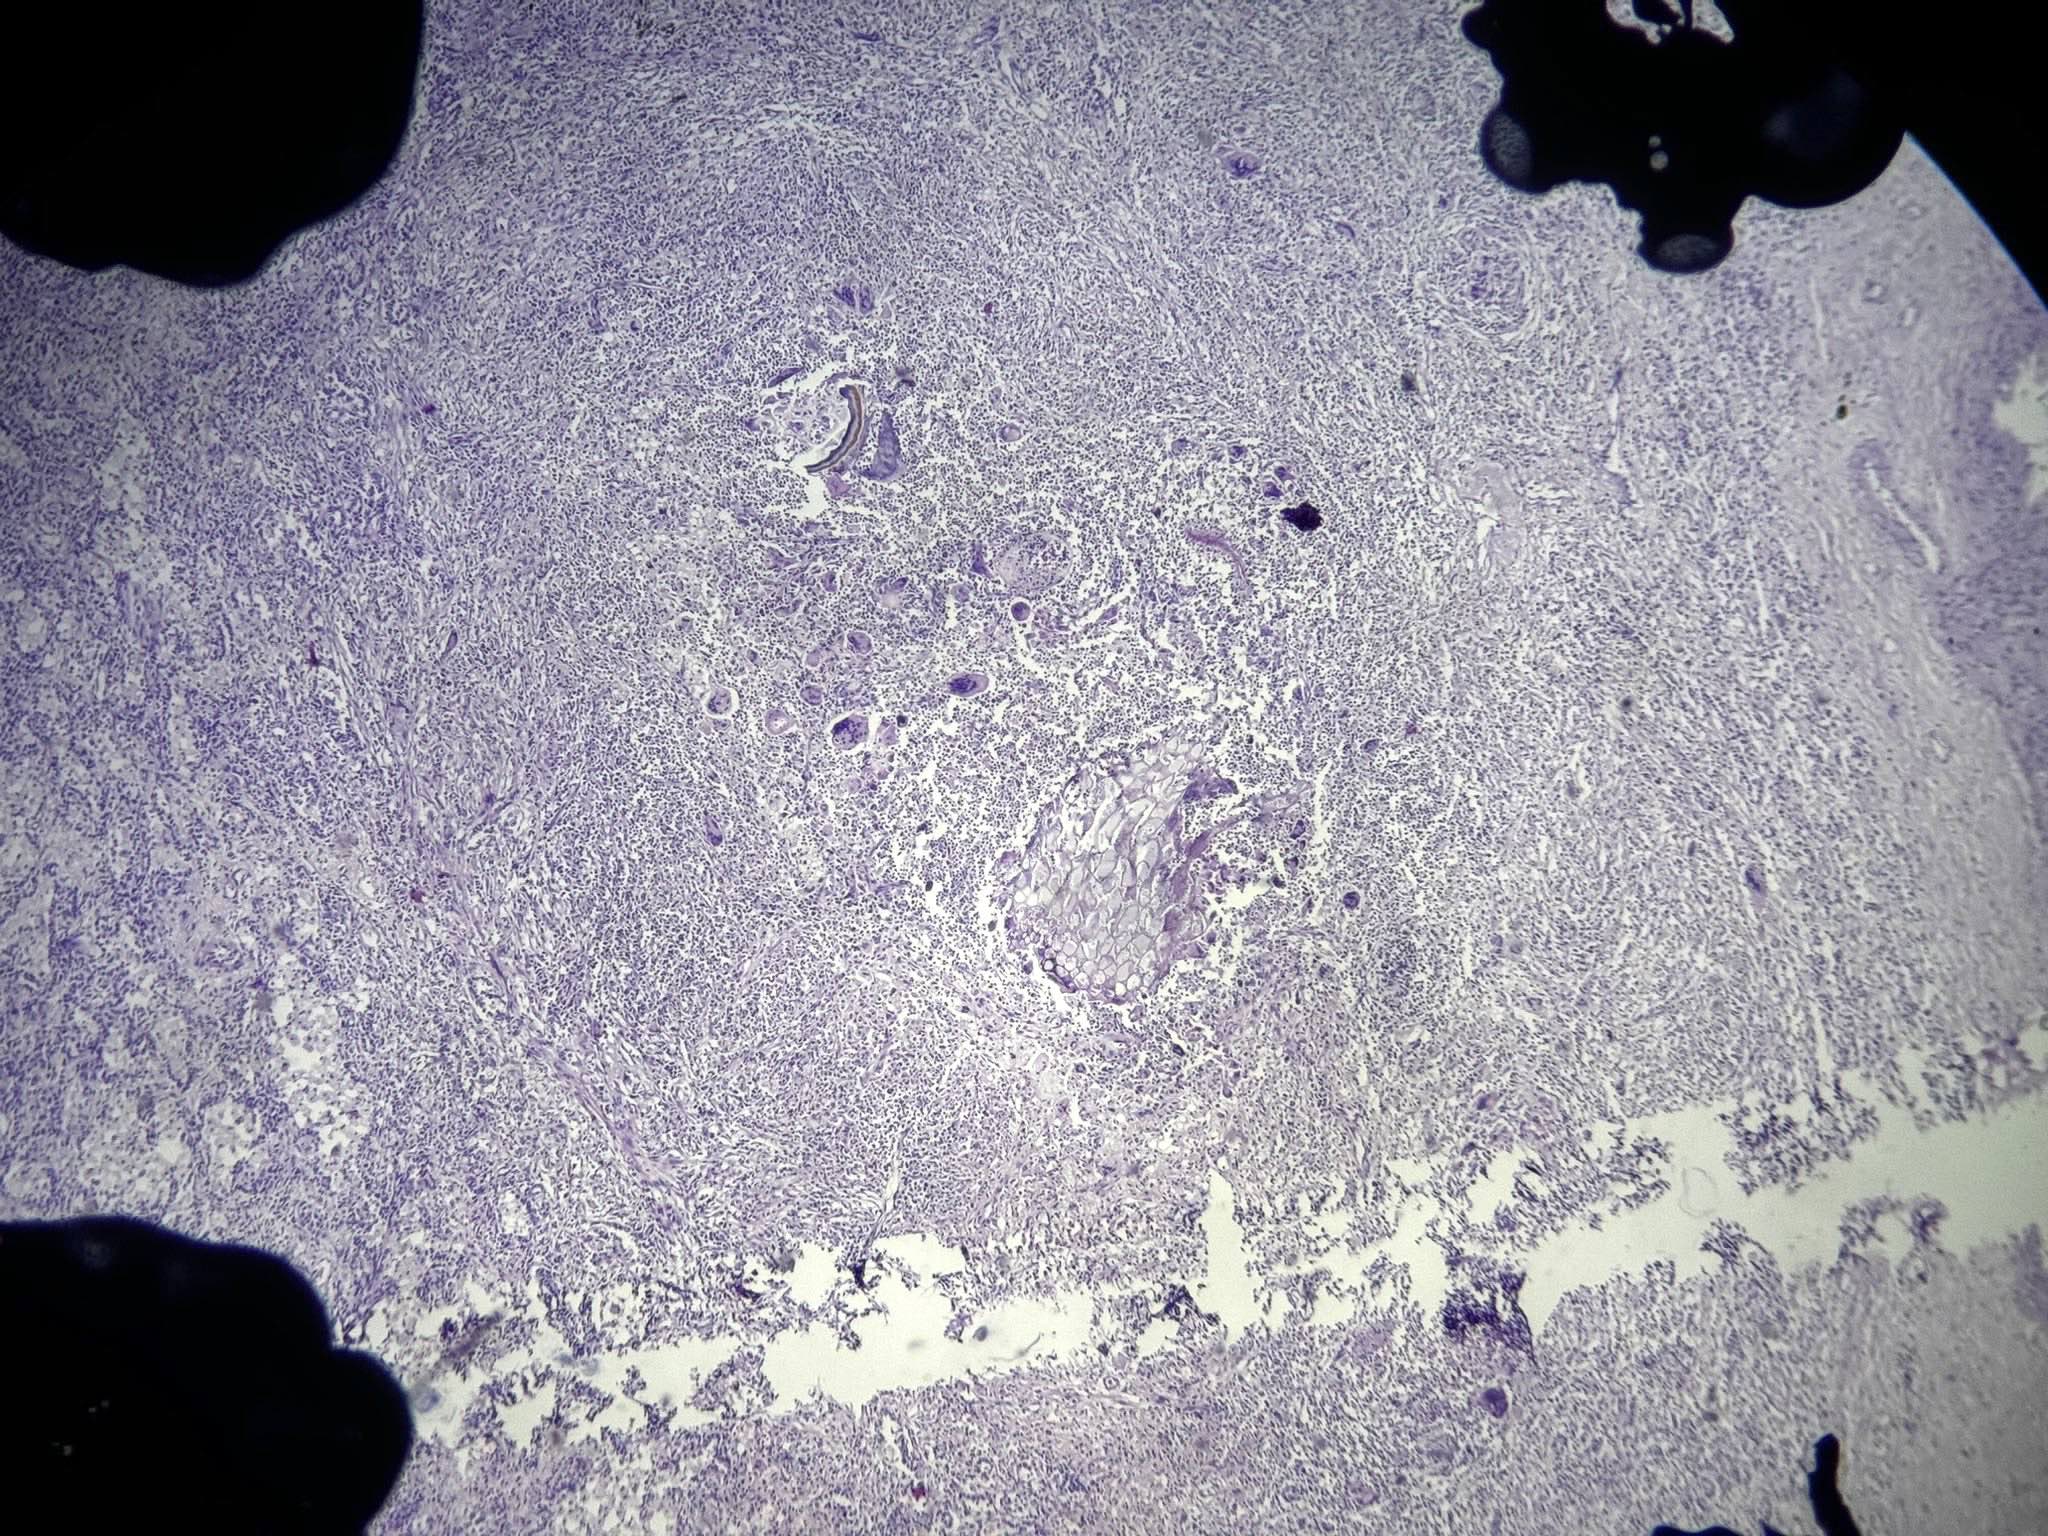

Microscopic (histologic) images

An 80 year old man presented with dyspnea, altered mental status and evidence of urinary tract infection. He was hospitalized in an intensive care unit for 2 weeks. The patient later developed fever, hypoxemia and new infiltrate on chest radiograph. An autopsy was performed and the lung showed the above histomorphology. What is the likely diagnosis?

- Bronchopneumonia

Practice answer #1